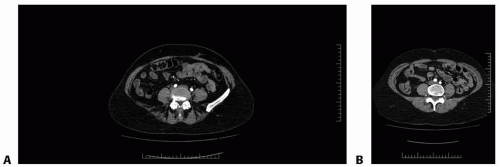

The free TRAM flap is based off the deep inferior epigastric vessels. The pedicle originates from the external iliac artery and then travels cephalad to enter the lateral and deep surface of the rectus abdominis muscle a few centimeters below the arcuate line. Just above the level of the arcuate line, the vessels typically divide into a medial and lateral row and continue superiorly, sending perforating branches through the muscle to supply the overlying skin and fat (FIG 1A,B).3,4

Having this preoperative understanding of the vessel anatomy for each individual patient can help to guide the decision between doing an MS-3 perforator flap (FIG 2A), which is our preference, and flap that includes muscle to incorporate additional perforators (FIG 2B).